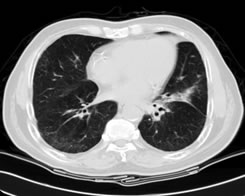

左肺下叶肺癌

放疗前放疗后